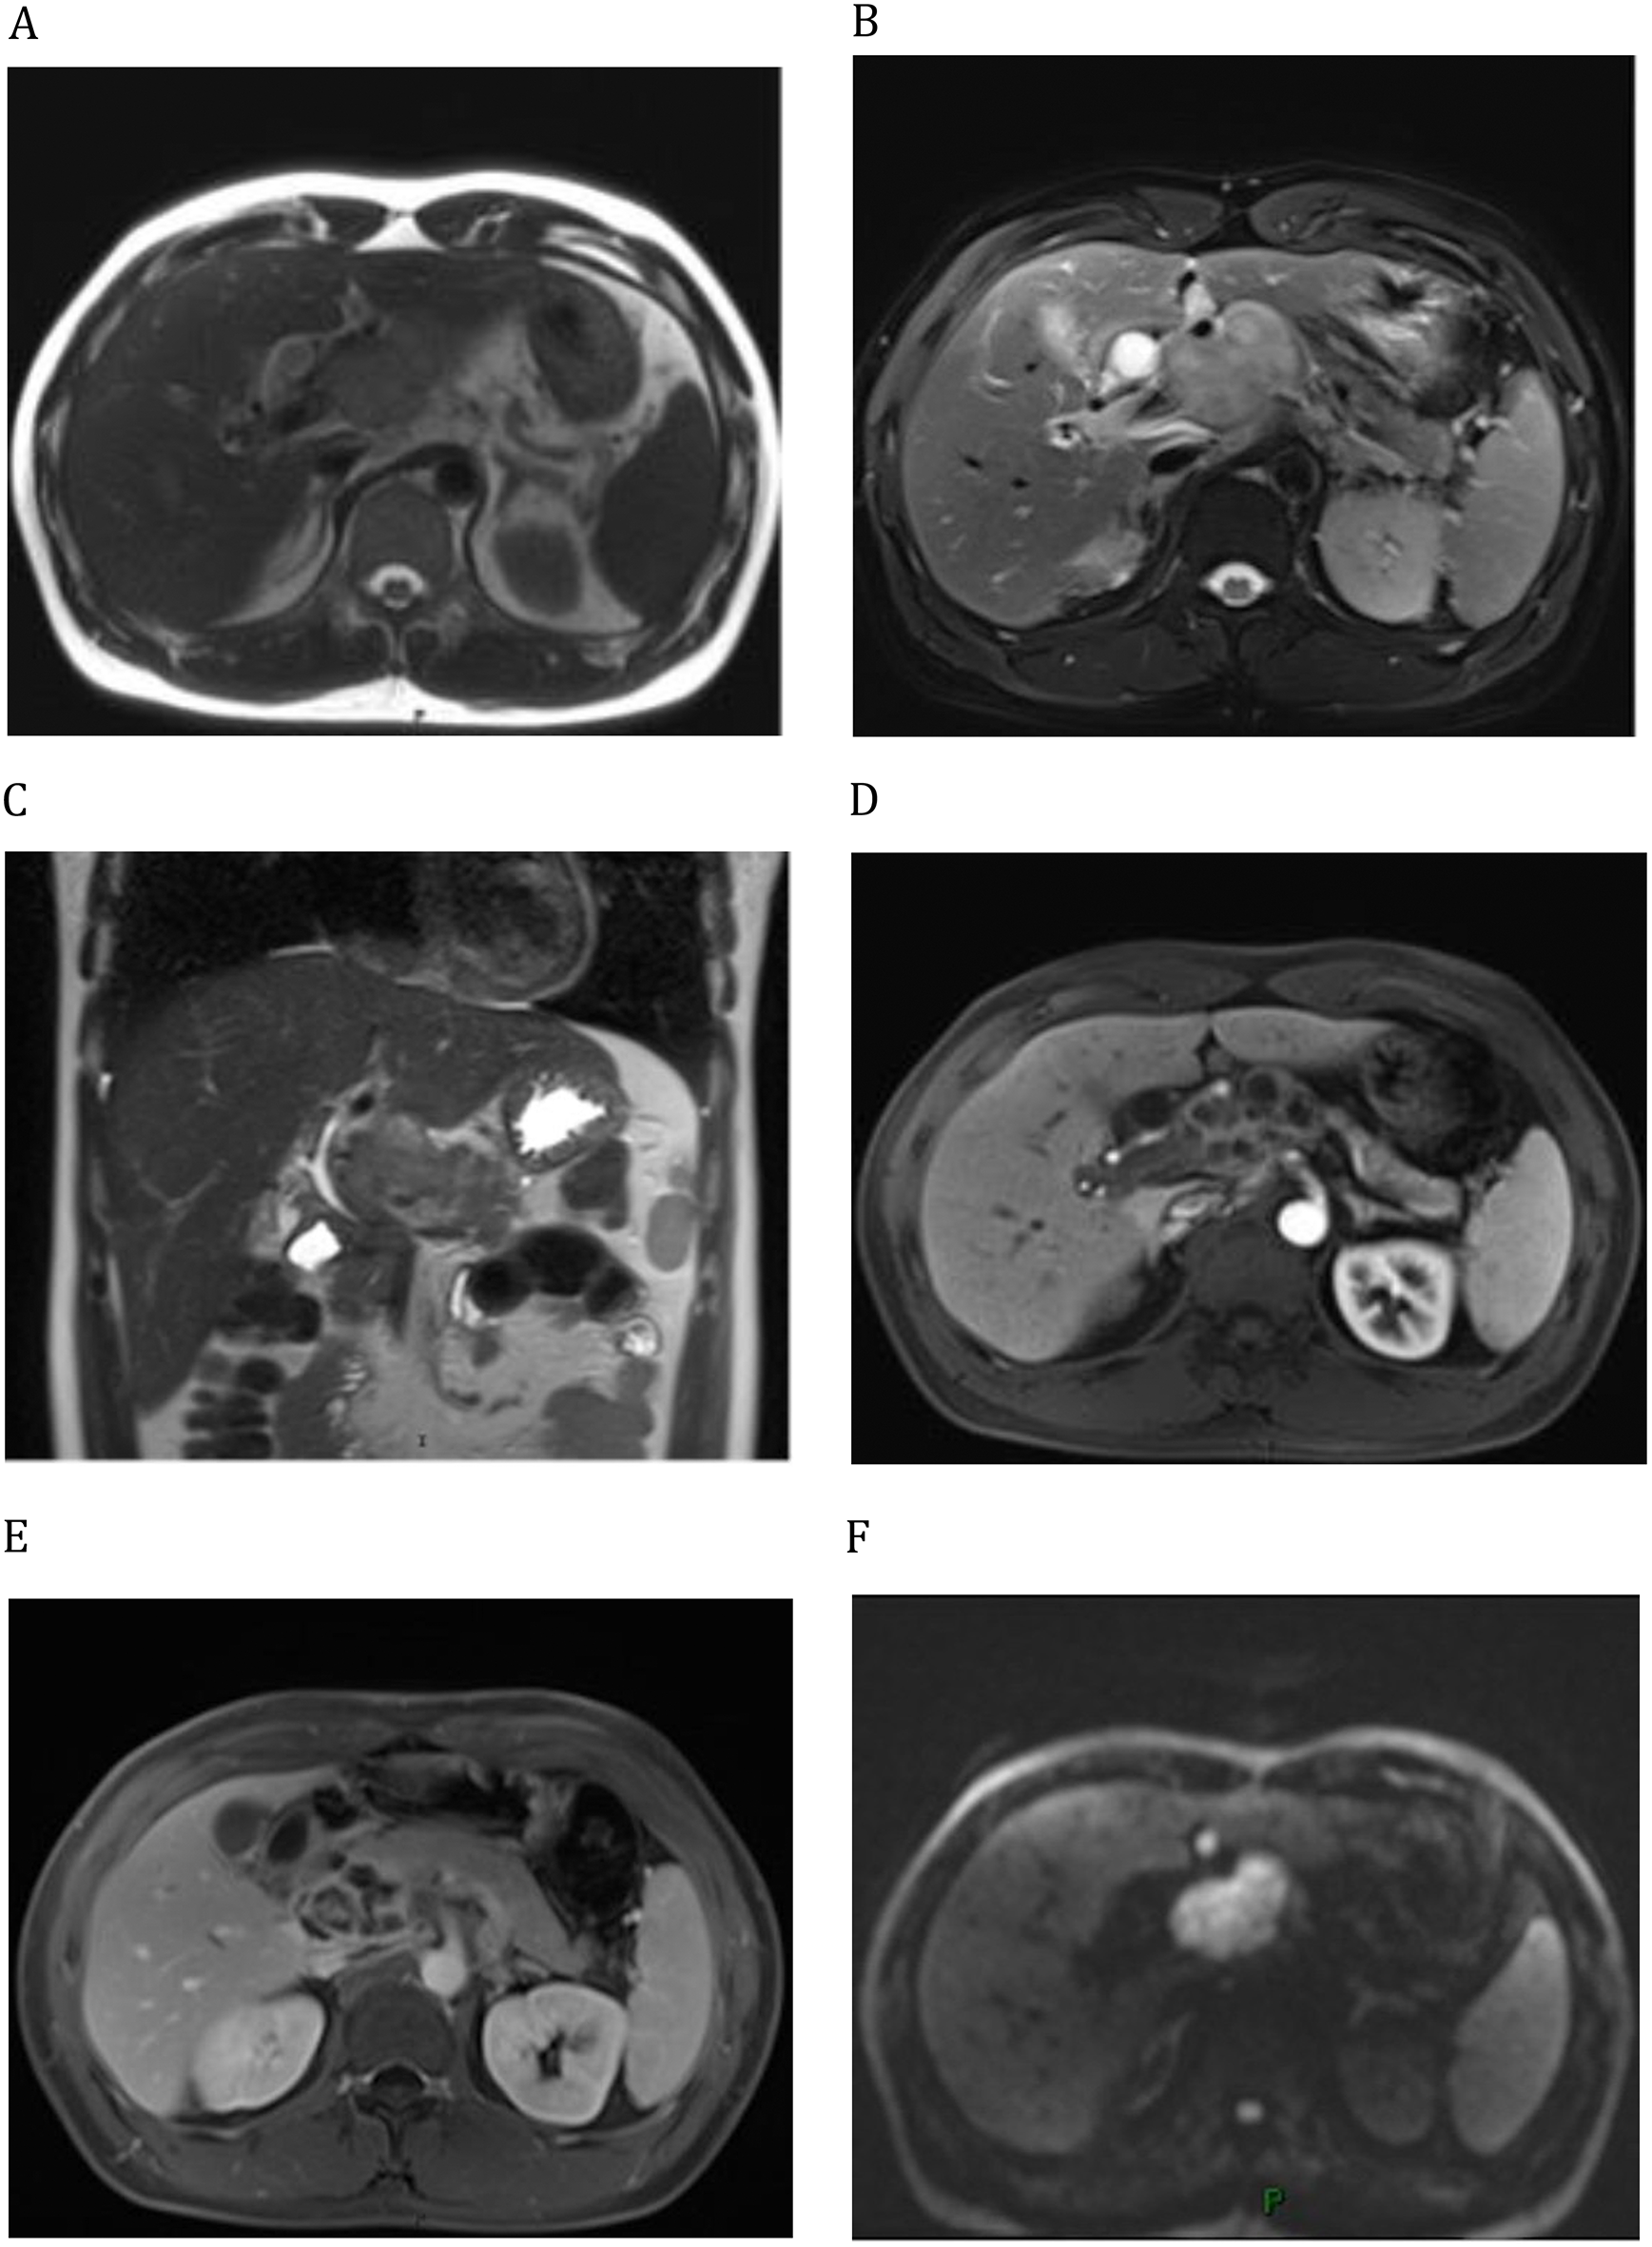

A case report of pancreatic tuberculosis: arterial infusion of isoniazid as an adjunct to oral antituberculosis medications has demonstrated promising therapeutic efficacy | BMC Infectious Diseases